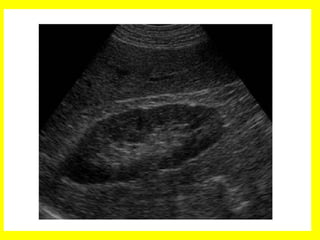

Ecografía abdominal. Es el examen no invasivo

más utilizado en la actualidad, pues permite

confirmar o descartar la obstrucción a nivel

renal y a diferenciar con otras causas los

defectos de llenado, observando en la

urografía, tales como tumores o coágulos.